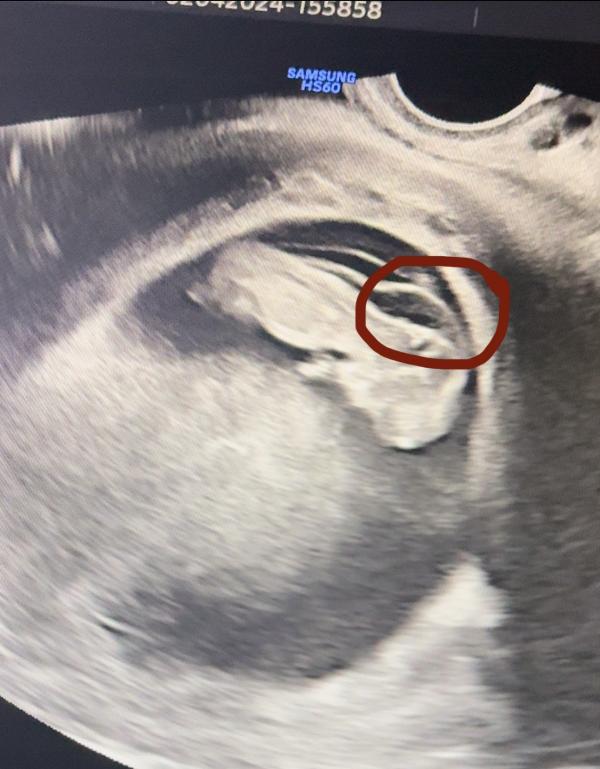

2.04 моя жизнь разделилась на до/после. Активно готовилась к семейной фотосессии, сделала маникюр/педикюр, получила ответ от лаборатори «пол малыша», вечером заехала на обычное узи (сделать свежие снимки малыша).

Ходченко обнаруживает увеличение зоны ТВП (складочка на затылке малыша). 3.8 мм при норме до 2...